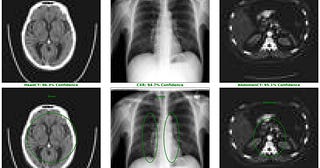

Accelerating DenseNet-121 Inference NVIDIA

Part 2: A MedNIST case study on accelerating medical imaging workflows with GPU-native pipelines

Aug 16 •

Kopal Garg